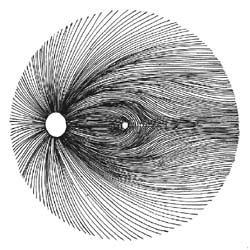

Nervová vlákna

Jsme schopni sledovat vrstvu nervových vláken v každodenní praxi bez nákladných přístrojů? Ano!

Vyšetření vrstvy nervových vláken indirektní biomikroskopií

- štěrbinová lampa s paprskem rovnoběžným s osou našeho pohledu

- 60-90 D čočka nebo čočka Goldmanova

- Pacient v mydriáze

Na snímku vidíme nastavení ramene štěrbinové lampy rovnoběžně s osou našeho pohledu. Pacient se dívá druhým okem 15 stupňů směrem temporálně.